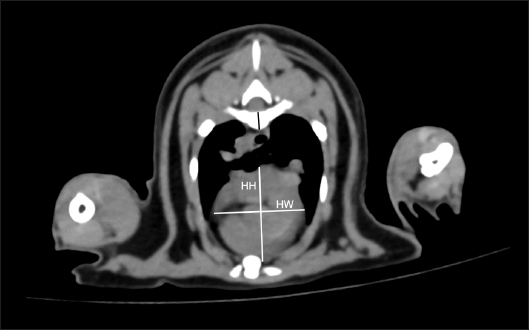

On cross-sectional images at the carina level, thoracic height/width ratio (THW) was determined as described previously (Uehara et al., 2009). A manual drawing using a digital caliper from the ventral border of the vertebrae to the sternum was performed to identify the thoracic height (TH). For the thoracic width (TW), a digital caliper was used from the right to left thoracic wall at the widest part and perpendicular to the TH as shown in Figure 2. THW was then calculated. Relative heart area (RHA) was evaluated by manually drawing the outline of the heart to evaluate the heart area (Fig. 3A). For the thoracic area (Fig. 3B), manual drawing was performed as described previously (Uehara et al., 2009). Finally, RHA was then calculated as the ratio of heart area to thoracic area at the carina level. Transverse vertebral heart score (tVHS) was determined by manual drawing using a digital caliper. Heart height (HH) was the height of the heart and heart width (HW) was the widest distance perpendicular to the HH. The ratio of the sum of HH and HW to the height of the vertebral body at the carina level was then calculated as tVHS (Fig. 4). CT vertebral heart score (ctVHS) was evaluated on the sagittal plane images. The measurement method was performed in the same way as on radiography (Lister and Buchanan, 2000) (Fig. 5). All CT measurements were performed by the same experienced radiologist using the same image archiving PACs system through DICOM viewer software.

Fig. 4. tVHS measurement methods. tVHS was measured on cross-sectional CT image at the carina level. Heart height (HH) was the height of the heart. HW was the widest distance perpendicular to HH. The ratio of the sum of HH and HW to the height of the vertebral body (black line) at the carina level was then calculated as tVHS. tVHS: transverse vertebral heart score; CT: computed tomography; HH: he.